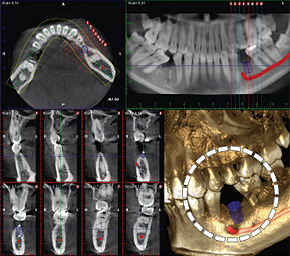

インプラント治療

インプラントを埋入する部位の骨の高さや幅、神経との位置関係を立体的に把握することで、より正確かつ安全な治療計画を立てることができます。

親知らずの抜歯

親知らずを安全に抜歯するためには、あごの中を通る神経や隣の歯との位置関係を正確に把握することが重要です。CT撮影を行うことで、それらをより明確に確認できます。

埋伏歯の診断

あごの中に埋まっている歯の位置や向きを立体的に診断できます。

CTとは「Computed Tomography(コンピュータ断層撮影)」の略で、X線で撮影した画像をもとにコンピュータで立体(3D)画像を作成する装置です。通常のレントゲンでは分かりにくかった部分も、CTによる立体画像ならより詳しく診断できます。

- 分かりやすい3D画像で症状をご説明します

- 歯や骨の内部まで立体的に確認できます